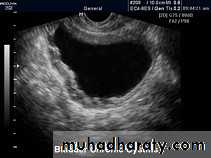

US :-

shows echo-free cystic lesion with posterior enhancement.